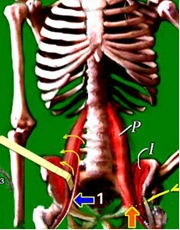

Korta höftböjare:

Musklerna börjar från samtliga kotor i ländryggen, är muskeln sammandragen så förhindras kotledernas naturliga rörlighet